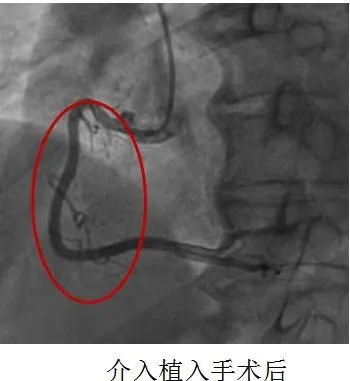

20分钟后患者导丝通过病变血管堵塞的血流恢复。

12点27分手术顺利结束,患者安返ccu病房。